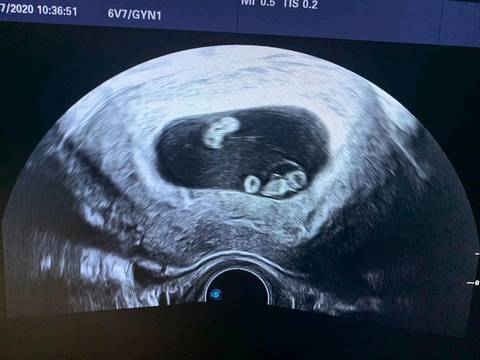

单卵双胎,单卵双胎b超

单胎变双胎!同卵双胞胎!祝大家好孕!_b超_建档_双胞胎

付锦华 文章列表 一,先了解一下双胎类型:双卵双胎和单卵双胎 1,双卵

单卵双胎b超

单卵双胎b超图片

单卵双胎早期b超图

一个孕囊双胞胎b超图

单卵双胎早孕超声图片

单卵双胎图片

单卵双胎九周图片

单卵双胎的彩超图片